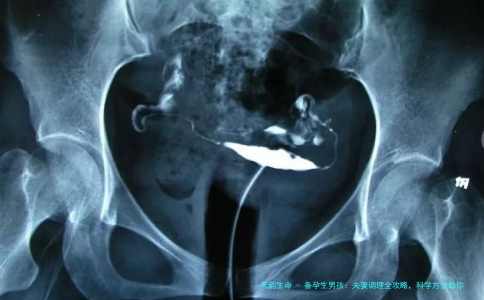

首先,咱们得了解一下生男孩的科学依据。生物学上,精子分为带Y染色体(生男孩)和X染色体(生女孩)两种。Y精子游得快但寿命短,X精子则相反。这就意味着,如果性行为时机选得好,比如在排卵期附近,Y精子更容易抢先到达卵子。我有个朋友张夫妇,他们就是通过精准计算排卵日,成功怀上了男宝。数据显示,调整性行为时机可以提高生男孩几率约10-15%,但这并不是绝对的,因为个体差异很大。